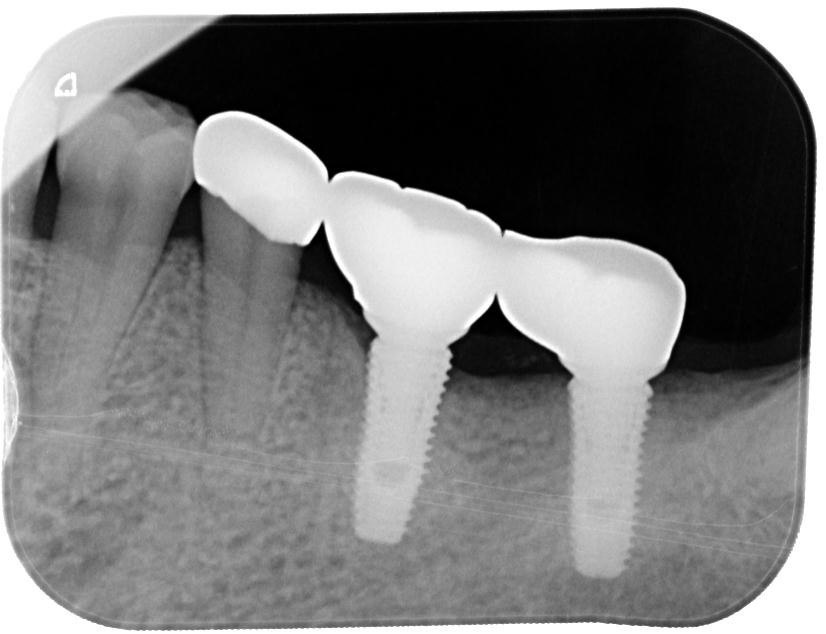

▲植牙方式重建:左下第一大臼齒、左下第二大臼齒

術後多年追蹤下,在根尖周圍X光片可見齒槽骨、植牙的位置都維持在穩定的狀態。